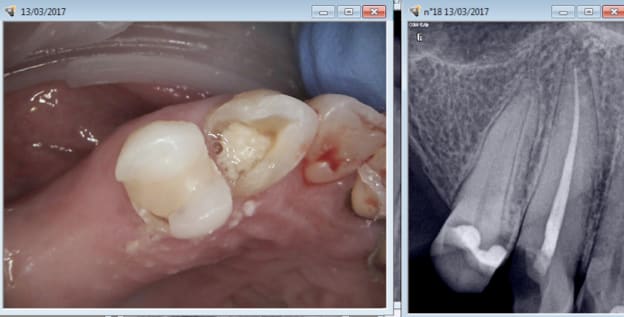

Casa je viens encore de reprendre un de tes traitements. Appliques toi merde ! -)))

Ici les 2 vont avoir droit à leur ic coiffe ( CMU) et pourtant un ic tarif CMU ca ne rapporte pas bésef.